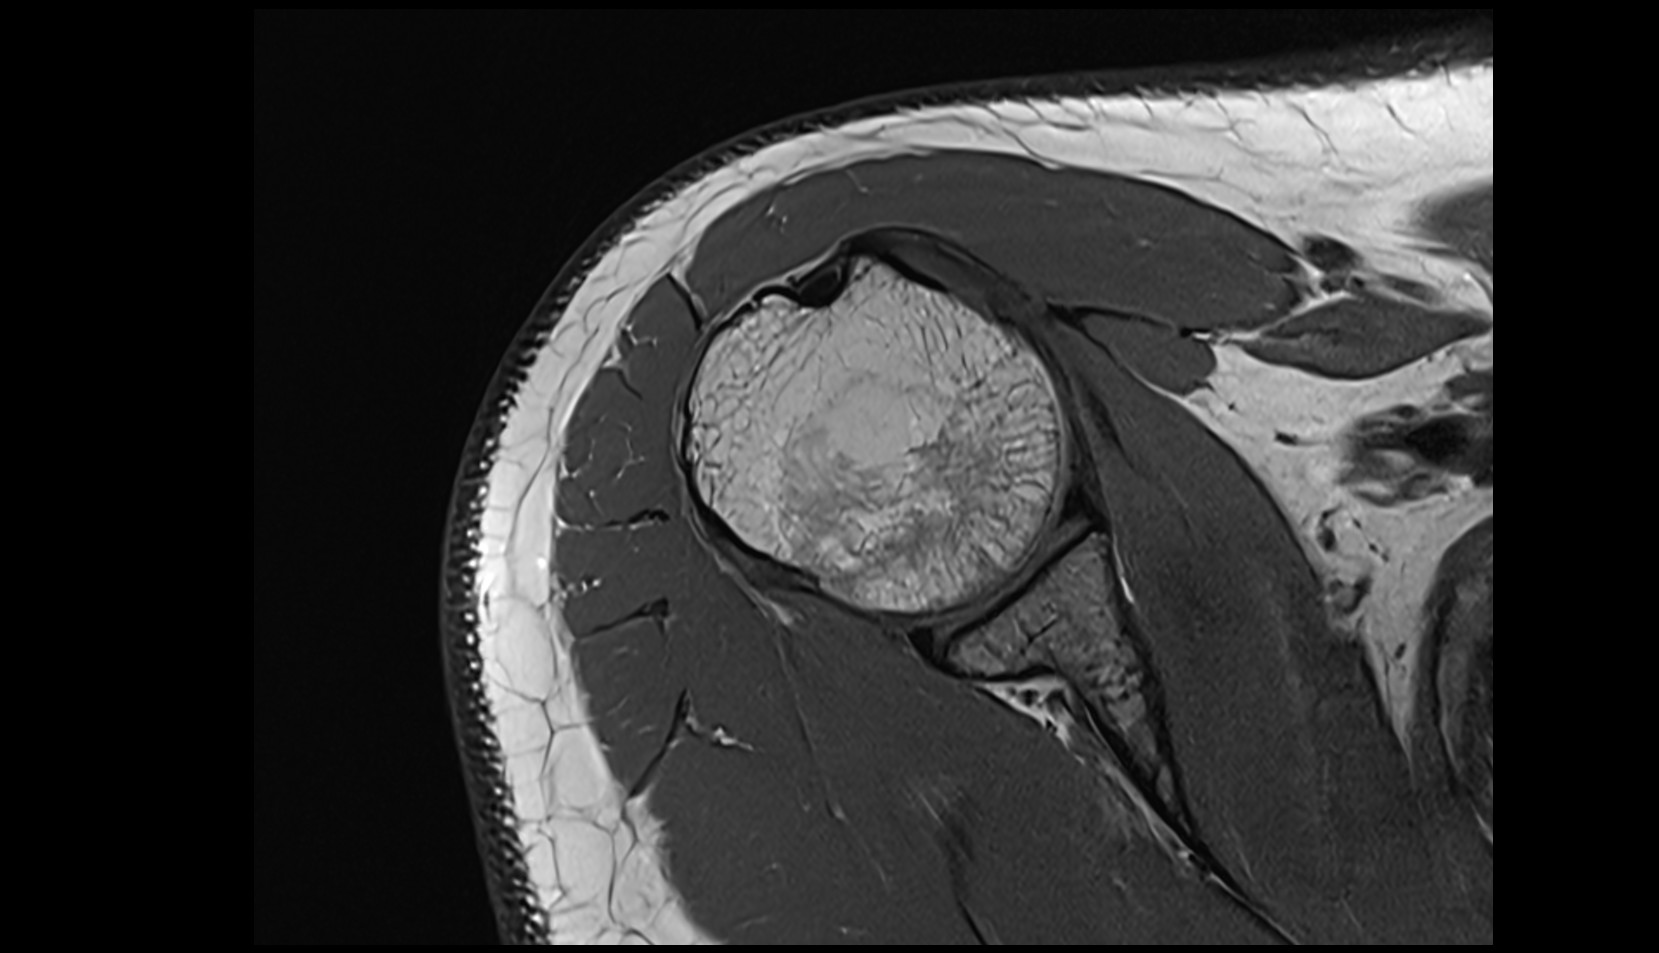

- Glenoid fossa

- Glenoid process of scapula

- Spine of scapula

- Acromion process of scapula

- Coracoid process of scapula

- Scapular body

- supraspinous fossa of scapula

- Subscapular fossa

- Neck of scapula

- Humerus

- Head of humerus

- Glenoid labrum

- Shoulder joint (glenohumeral joint)

- Supraspinatus tendon

- Infraspinatus tendon

- Subscapularis tendon

- Adipose tissue (Shoulder)

- Subacromial space